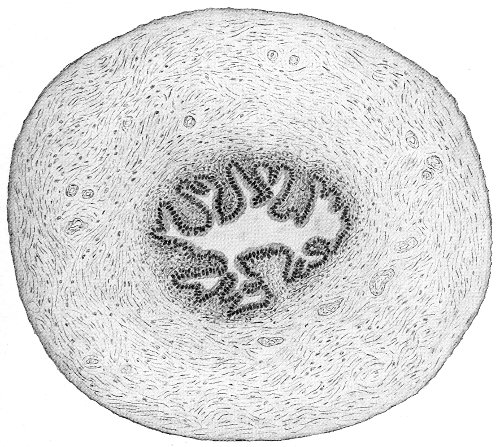

The vagina extends, as a transverse slit in the pelvic floor, upward and backward, approximately in the direction 60 of a line drawn from the ostium vaginæ to the fifth sacral vertebra. It is approximately parallel with the conjugate of the brim, so that when the woman is erect the long axis of the vagina is inclined at an angle of 60° to the horizon. The vagina is not a vertical open tube: it is a slit in the pelvic floor, in health always closed by the accurate apposition of the anterior and posterior walls (Fig. 21). The anterior vaginal wall is about 2½ inches long in a vertical mesial line. The posterior vaginal wall is about 3½ inches long. The vaginal walls are triangular in shape, being broader above than below. The shape of the normal vagina at the pelvic outlet is shown by Fig. 23. The section here shows the vaginal 61 slit of the shape of the letter H. The portions of the slit extending backward and somewhat outward are called the vaginal sulci or furrows. They are directions of diminished resistance in which tears are liable to occur.

Fig. 23.—Section illustrating the characteristic form of the vaginal cleft (Henle): Ua, urethra; Va, vagina; L, levator ani; R, rectum.] 62